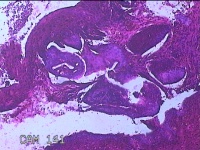

宫颈12点组织

性别

女

年龄

46岁

临床诊断

人乳头瘤病毒感染

一般病史

人乳头瘤病毒其他12高危型阳性

标本名称

大体所见

灰白暗红色组织0.8x0.5x0.2cm一块。